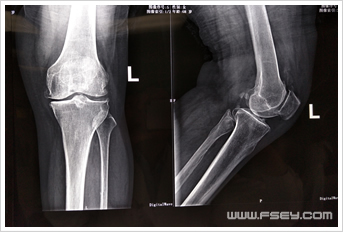

禅城的刘阿姨今年68岁,但双膝关节反复疼痛已有近十年。曾多次至佛山各大医院就医,当医生告诉她双膝关节退变严重,彻底解决问题需要行全膝关节置换手术时,刘阿姨因为害怕而拒绝医生建议的手术方案,坚持要求保守治疗,所以双膝疼痛一直未能痊愈,直到刘阿姨来到我院骨科住院治疗。完善膝关节X光片及MR等相关检查后,刘学东主任认为:患者老年病人,体型相对肥胖,双膝关节增生退变并以内侧间隙变窄为主,外侧间室及髌股关节面尚可,膝内翻小于15°,膝关节韧带结构基本完整,呈典型老年骨性关节炎变现,有膝关节置换手术指针。刘学东主任耐心和刘阿姨沟通病情,得知老人主要是不能接受全膝关节置换的创伤及术后康复锻炼时的疼痛,刘主任提出了行左膝关节单髁置换的手术方案,通过细心讲解该手术微创的特点,征得患者及家属理解并同意手术治疗方案。手术历时约40分钟,术后当天刘阿姨就下地行走,伤口疼痛完全在接受范围内,刘阿姨终于开心的笑了。

术后 术前